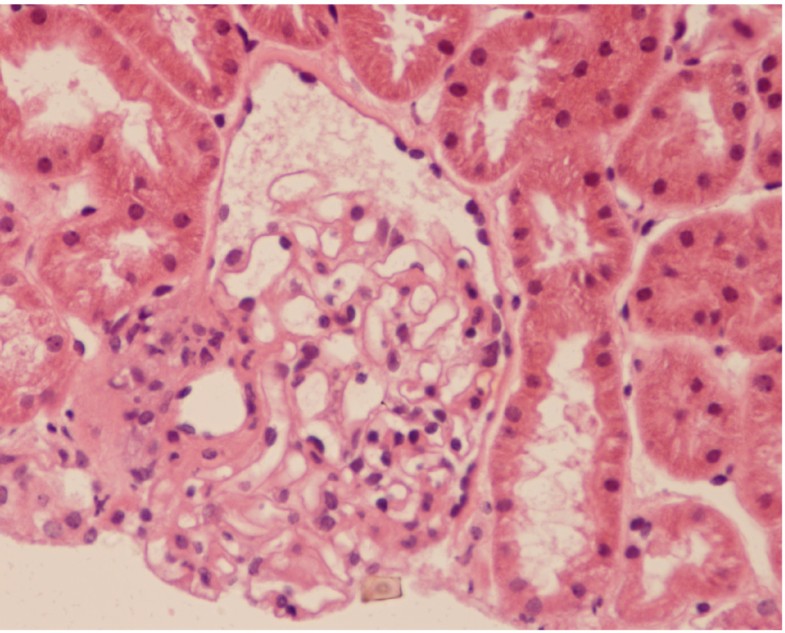

capillary basement membrane thickening pathologyoutlines topic kidneydiabetes htmlDiffuse capillary basement membrane thickening diffuse and nodular glomerulosclerosis Causes glomerular disease arteriolar sclerosis pyelonephritis papillary necrosis similar between type I capillary basement membrane thickening the kidney the microangiopathy leads to thickening of the glomerular capillary basement membrane but also to the expansion of the mesangial matrix and thickening of the tubular basement membrane Several mechanisms are implicated in the pathogenesis of diabetic renal microangiopathy

basement Why basement membrane thickens in diabetes mellitus up vote 5 down vote favorite Untreated diabetes mellitus may lead to blindness and kidney failure because the basement membrane of small blood vessels in these organs thickens due to increased production of collagen and laminin capillary basement membrane thickening onlinelibrary wiley Anatomy PhysiologySignificant retinal capillary basement membrane thickening in hyperglycemic and normoglycemic diabetic prone DP BB Wistar rats Ultrastruct Pathol 35 97 105 CrossRef Web of Science Times Cited 2 Gundersen HJG Osterby R 1972